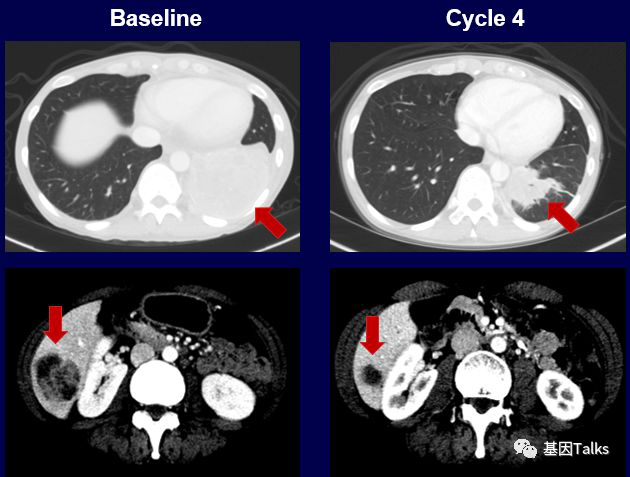

(1)1例肺癌合并SQSTM1-NTRK1融合:

(2)1例婴儿纤维肉瘤合并ETV6-NTRK3融合:

(3)1例分泌性乳腺癌合并ETV6-NTRK3融合: